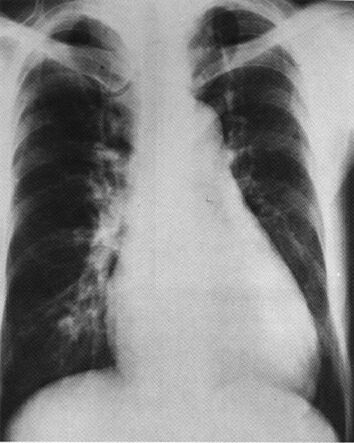

На рентгенограмме видны признаки увеличения левого и правого желудочков, признаки легочной гипертензии.